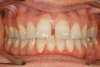

Décalage traité par gouttières

Début de traitement